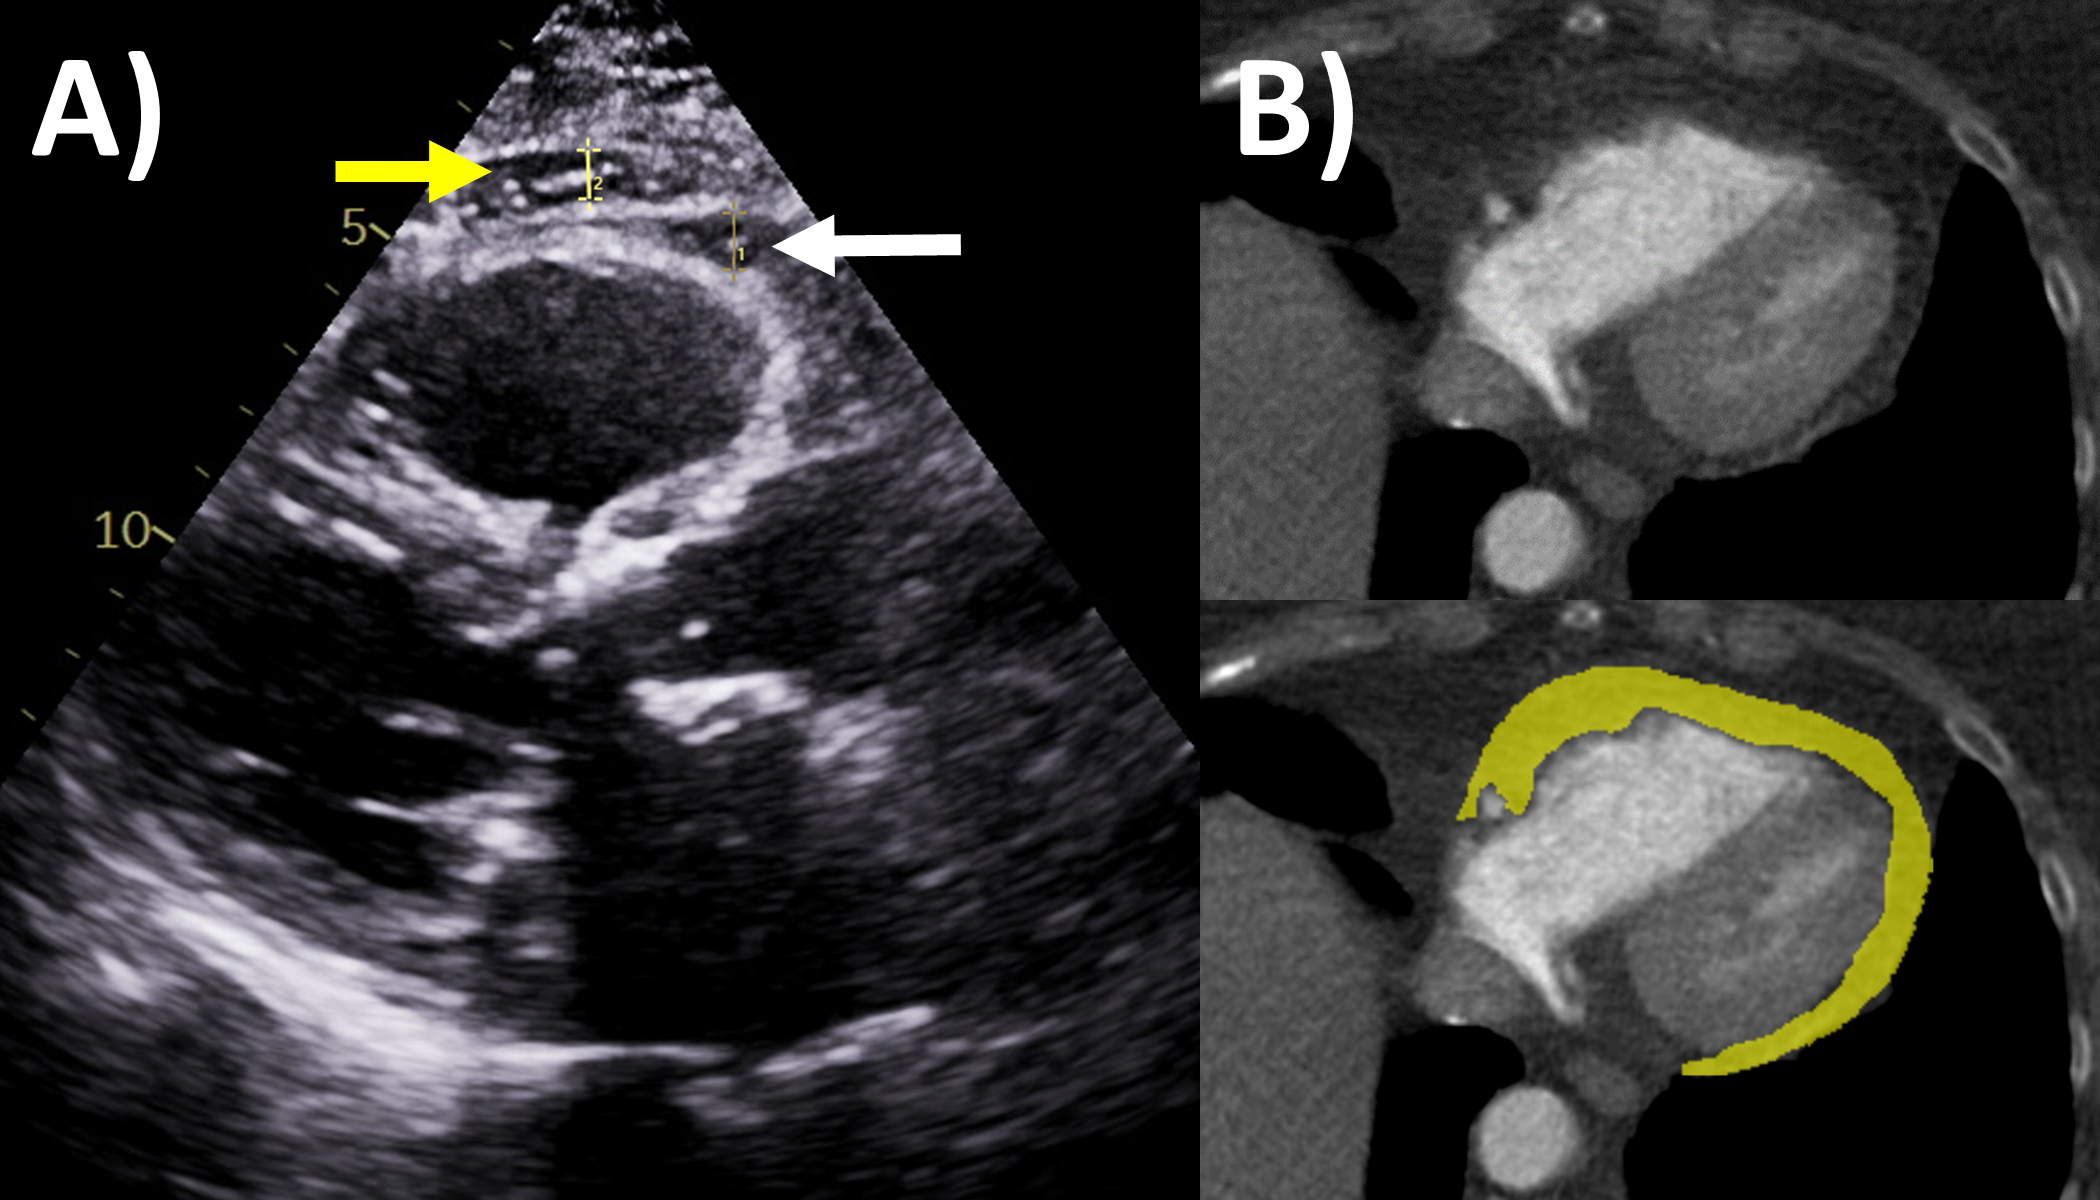

Pericardial constriction is a feared chronic complication of pericardial

disease, occurring in approximately 1–2% of pericarditis patients, sharing the

same etiology but often challenging to diagnose [1, 35]. Echocardiography is also

the first-line and often self-sufficient modality for evaluation of constrictive

physiology [2, 36]. The Mayo Clinic Criteria being the recommended algorithm for

diagnosing this entity that is frequently challenging to distinguish from

restriction or diastolic dysfunction, with several key findings shown in (Fig. 3)

[36, 37, 38]. The first part of the algorithm has the dual criteria of mitral inflow

E/A ratio

Fig. 3.Multi-modality imaging evaluation of constrictive pericarditis.

Echocardiography (A) dilated inferior vena cava (2.3 cm) with minimal

Of note, in the Mayo Clinic Criteria derivation study, the presence of

respirophasic ventricular septal shift and either medial e’ velocity

Cardiac CT may assist with diagnosis of pericardial constriction if inconclusive by echocardiography alone [2]. Supportive findings include abnormal thickening 4 mm or more, pericardial calcifications (where CT is the best modality to assess this, although only 25–50% of constriction patients with calcifications), dilated inferior vena cava and atria, conical deformity of the ventricle(s), and extracardiac findings such as pleural effusion, ascites and hepatosplenomegaly [2, 45, 46, 47]. Pericardial calcification often has an irregular distribution, such as preferentially affecting the basal anterolateral left ventricle, right ventricular outflow tract, and adjacent to the mitral and tricuspid annulus [48]. If cine images of the cardiac chambers over one cardiac cycle are performed using retrospective ECG-gating, then respirophasic septal shift and wall tethering may be observed [2]. Perhaps just as valuable is CT’s role in the evaluation of the thoracic anatomy or extracardiac pathologies as part of pre-operative evaluation for pericardiectomy or other cardiothoracic surgeries, such as location of pericardial and aortic calcifications, and cardiovascular structures relative to the sternum which are especially important in redo cardiac surgery [49].

MRI is actually a valuable second-line but under-utilized imaging tool for

evaluating constrictive pericarditis [2]. Standard cine imaging with steady state

free precession or gradient echo sequences not only assess chamber size and

function, but also typical constriction findings such as abnormal

interventricular septal motion, wall tethering, conical ventricular deformities,

and dilated inferior vena cava, while free breathing sequences allows assessment

for respirophasic septal shift (Fig. 3) [2, 50]. Pericardial thickness often

increased in constrictive pericarditis can be assessed by these bright-blood

sequences or black-blood spin echo sequences, as well as dilated inferior vena

cava. Quantitative measures include lower short-axis cardiac area at

end-inspiration/end-expiration, and higher relative atrial volume index ratio

(left versus right) to be present in constrictive pericarditis [51, 52].

Acquiring phase-contrast sequences real-time over 10 seconds with free breathing

an detect mitral and tricuspid inflow, with